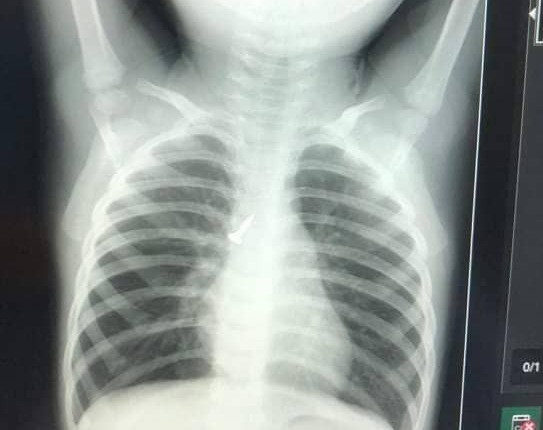

Bé trai đột ngột khó thở, tím tái sau buổi học

Bé trai gần 3 tuổi đi học về đột ngột quấy khóc, khó thở từng cơn, tím tái, người lịm đi.